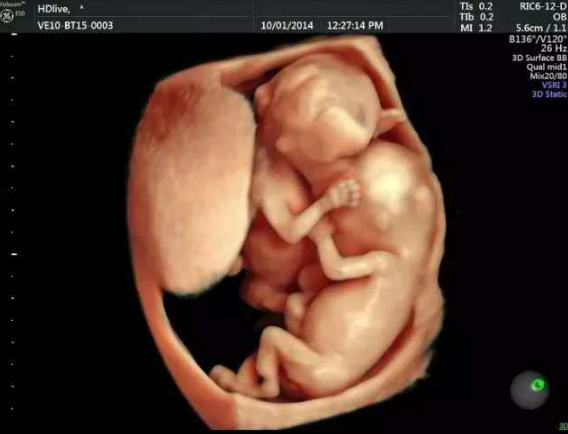

其实,就像朋友这样会对,怀孕四个多月了,那宝宝危害畸形的概率还是很大的,但具体影响有多大,还是要做个四维彩致畸率超才知道怀孕。

四维彩超是在怀孕24周左右做的,可以筛查胎儿颜面畸形、内脏畸形、四肢危害畸形等,怀孕五周抽电子烟有危害吗,孕妇抽烟对胎儿有什么影响大吗而她现在是怀孕四个月,也就是怀孕16-18周了,我让她提前咨询医生,预约四维检查了。